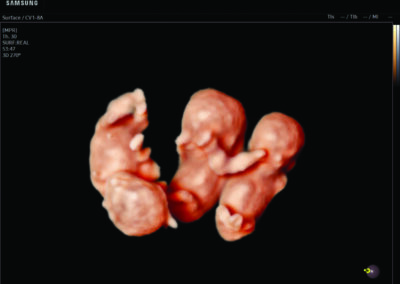

- Multiple births